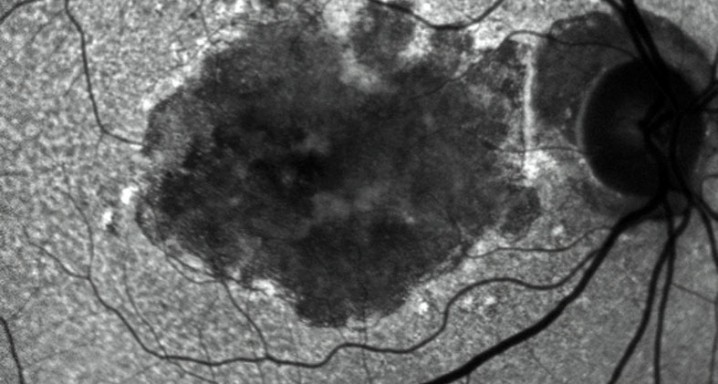

El equipo de investigadores del Institut de la Màcula, liderado por el Dr. Jordi Monés e integrado en el estudio EYE-RISK, ha publicado en Ophthalmology Retina, uno de los principales canales de difusión de la American Academy of Ophthalmology, las conclusiones de un estudio destinado a definir diversas clases de atrofia geográfica, según los condicionantes genéticos y ambientales. La atrofia geográfica es la forma avanzada de la degeneración macular asociada a la edad (DMAE). El estudio publicado se ha llevado a cabo entre 196 pacientes vinculados al EYE-RISK, un programa financiado por la Comisión Europea que implica a once instituciones continentales, entre las cuales la Barcelona Macula Foundation (BMF).

Los resultados del análisis han identificado 3 subgrupos de atrofia geográfica, caracterizados fundamentalmente por la localización de la atrofia y el tipo de drusas (acumulaciones de material celular depositadas en la retina, asociadas a la DMAE) que presentan. El primer subgrupo se caracteriza por un alto riesgo genético, asociado con drusas de grandes dimensiones y atrofia foveal; el segundo subgrupo suele tener bajo riesgo genético, atrovia foveal y pocas drusas. El tercer subgrupo mostraba, entre otros, altos niveles de de ARMS2, alto riesgo genético, pseudodrusas reticulares y atrofia extrafoveal.

Con estas conclusiones, parece claro que los tratamientos de la atrofia geográfica han de modularse en función del individuo: hemos descubierto que aquello que hoy consideramos una “misma” enfermedad puede incluir diferentes evoluciones patológicas. Así que una misma terapia podría no funcionar para todos los pacientes.